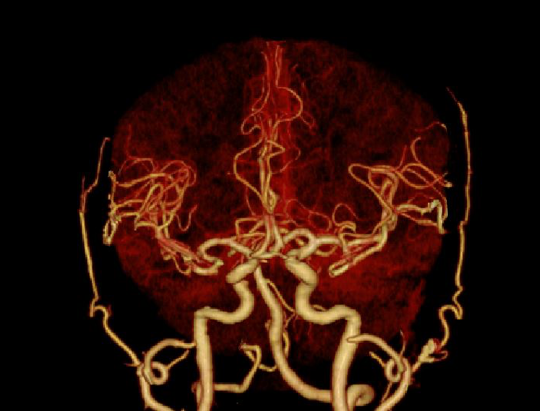

半秒单圈轴扫即可完成全脑扫描,多重软硬件技术克服锥束伪影和散射伪影挑战,提升软组织密度分辨率,改善颅底结构显示效果

3D打印精密工艺三维防散射栅格、Real 3D Full大锥角重建算法等多重硬件、软件技术协同,克服宽体探测器的核心技术挑战,天河640单圈扫描即可获得高质量的全脑、全冠脉轴扫图像